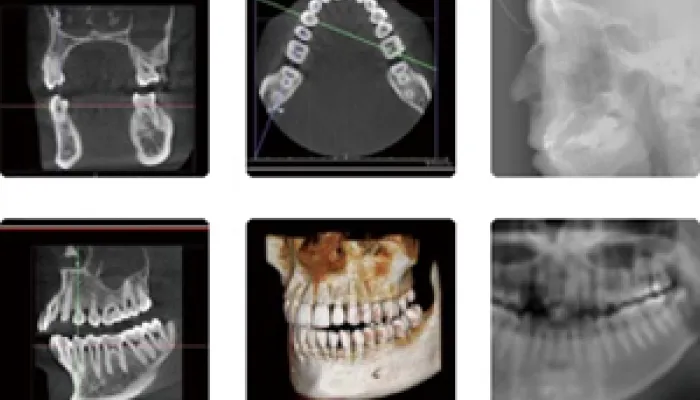

世界最高峰のX線CT診断装置Fine Cube E2を導入

今までの一般的なレントゲンで見ていたものは平面的な画像でしかありませんでした。

虫歯や歯周病、顎関節の病態をおおまかに捉えることは可能ですが、あくまでも影絵なので、骨の幅や形などを見ることは絶対にできません。

対してCTは立体的にこれをとらえることができるため歯科医師はさらに詳細に診断を行えますし、説明を受けられる患者さんにもご自身の現状をわかりやすく伝えることができます。